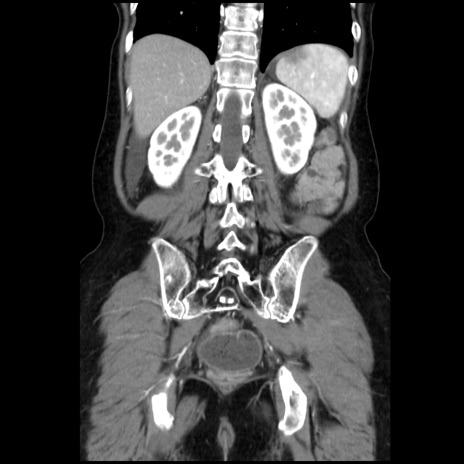

横断像

【症例】40歳代 女性

【主訴】上腹部痛、嘔気・嘔吐

【現病歴】約9時間前頃から急に上腹部痛、嘔気、嘔吐が出現。改善しないため救急要請。

【既往歴】子宮頚癌(広汎子宮全摘術、放射線療法)、腸閉塞

【身体所見】腹部:平坦、軟、腸雑音亢進、上腹部を中心に腹部全体に圧痛あり。

【データ】WBC 8400、CRP 0.03